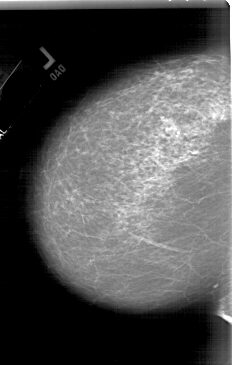

A_1773_1.LEFT_CC

LEFT_CC LINES 6196 PIXELS_PER_LINE 3931 BITS_PER_PIXEL 12 RESOLUTION 43.5 NON_OVERLAY